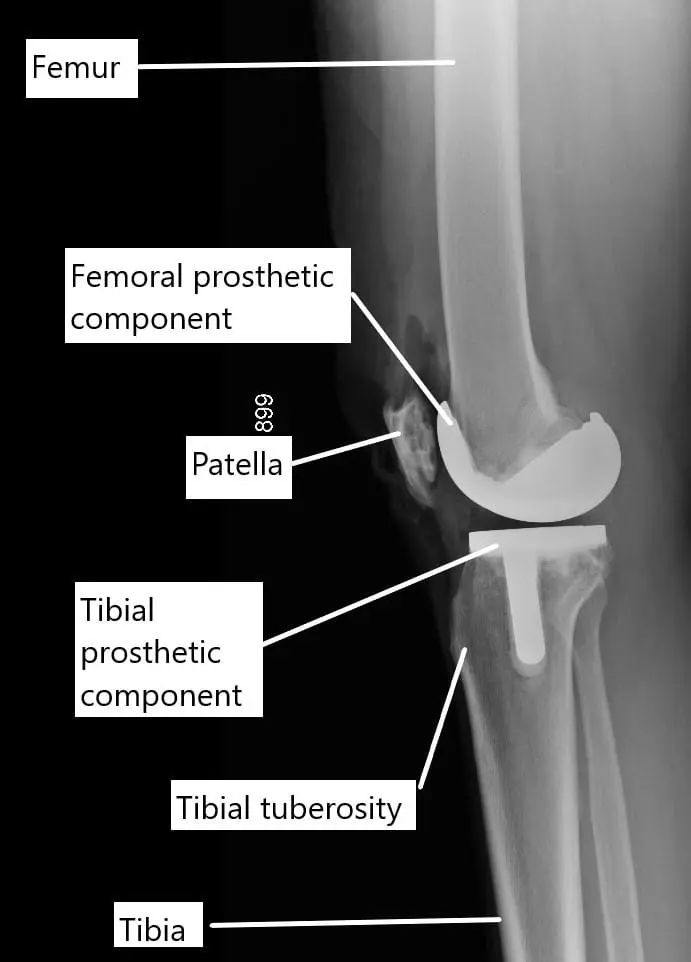

Before delving into exercises, let’s briefly understand knee replacement surgery. During knee replacement, damaged or diseased parts of the knee joint are replaced with artificial components made of metal and plastic. This procedure aims to relieve pain, restore function, and improve mobility for individuals with severe knee conditions.

During the surgery, the arthritic ends of the knee joint are replaced with prosthetic metal alloy and plastic parts. The surgery involves cutting of the tissues and the bone to fix the prosthetic parts. A bone cement is used to fix the prosthetic parts at the ends of the thigh bone, shin bone and the undersurface of the patella.

X-ray showing a total knee replacement.